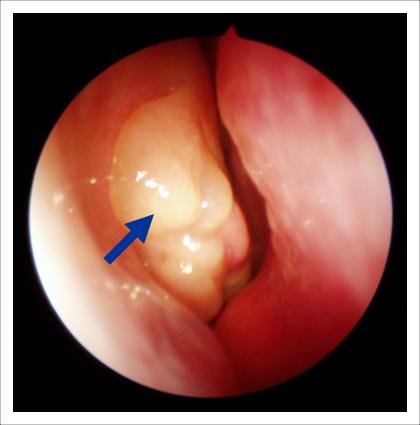

Физикальное обследование включает в себя осмотр носоглотки с помощью специального инструмента — риноскопа. Этот метод позволяет врачу визуально оценить состояние лимфоидной ткани, определить степень ее увеличения и наличие воспалительных изменений. В некоторых случаях может потребоваться использование эндоскопии, которая дает более детальную картину состояния носоглотки.

- Рентгенография носоглотки: позволяет оценить размеры аденоидов и выявить возможные осложнения, такие как синуситы.